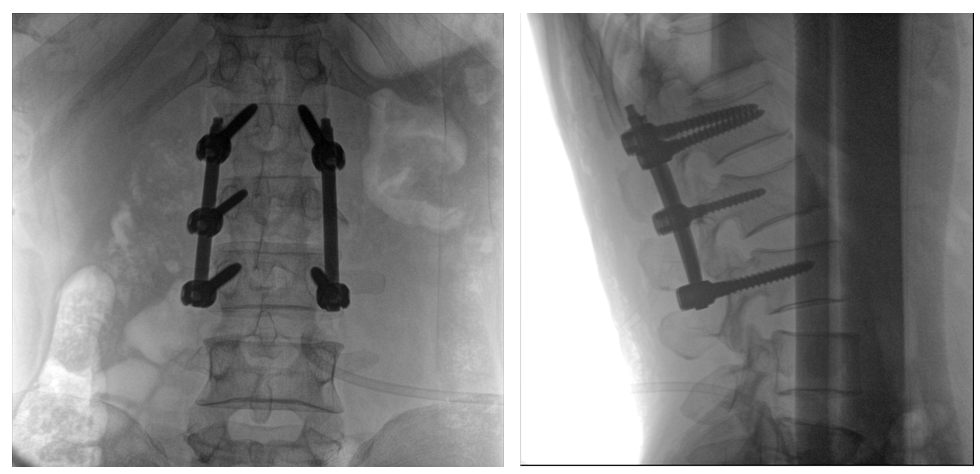

病例一:

患者不慎摔傷,傷后腰部疼痛,腰2椎體壓縮性骨折,遂以“椎弓根釘內(nèi)固定術(shù)”治療。椎弓根螺釘可以從椎體后方貫穿到椎體前方,達(dá)到椎體三柱固定,但是手術(shù)過(guò)程中要保對(duì)多節(jié)錐體進(jìn)行手術(shù),所以要求圖像要盡可能的展現(xiàn)出全節(jié)段腰椎。

一體式C形臂全節(jié)段腰椎臨床影像

普愛(ài)醫(yī)療PLX119C大平板一體式C形臂采用30CM×30CM的平板探測(cè)器,一般可一次性成像5節(jié)腰椎,呈現(xiàn)更廣闊的視野。使醫(yī)生一次性全面地觀察到傷椎及周圍椎體情況,使得手術(shù)效率更高、更準(zhǔn)確。